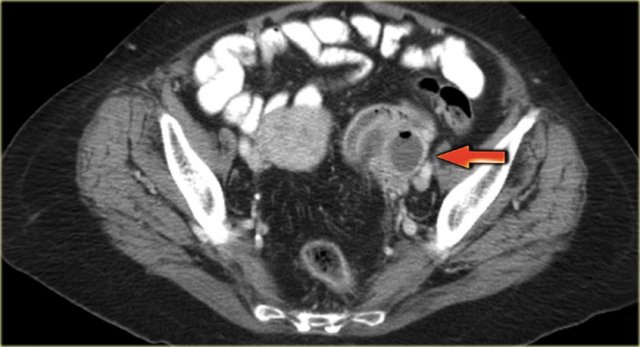

The CT image shows complex cystic masses in both ovaries.

While a serous cystadenocarcinoma may very well be bilateral, they are more often unilocular than multilocular.

Barely visible is part of a circumferential colorectal cancer (blue arrow).

Clearly visible are cystic implants on the peritoneal reflection (red arrow). These were cystic ovarian metastases of a colorectal cancer. This is an uncommon finding.